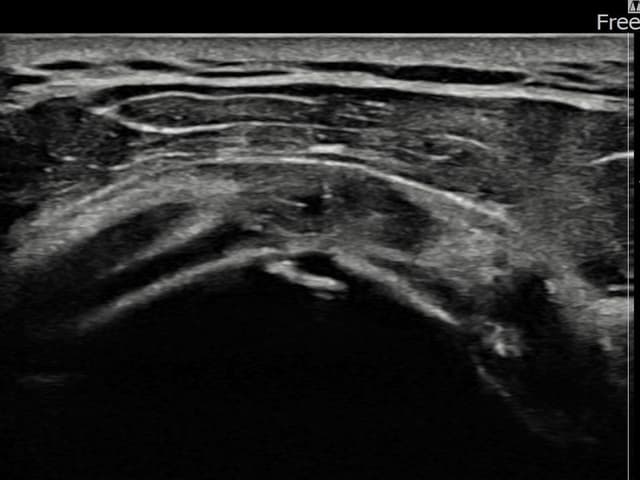

[経過期間: 23.07.18~23.09.14]

[縫縮術] 超音波検査にて左 棘上筋腱 광범위 部分断裂(15mm × 6mm (腱厚の約70%欠損))を確認。縫縮術施行後、腱の連続性が回復し、日常生活に復帰されました。